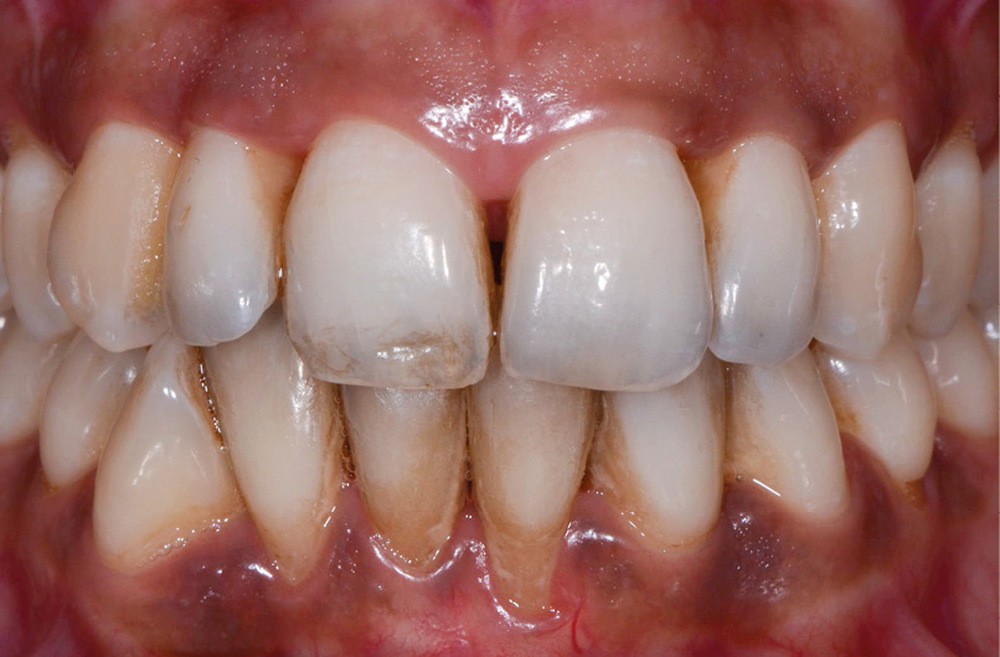

Elles intéressent la structure organo-minérale de la dent par incorporation de molécules colorées au sein du complexe amélo-dentinaire. Elles peuvent être liées à la prise de médicaments (fig. 2a), à des maladies génétiques ou congénitales. Elles peuvent également être la conséquence d’une pathologie pulpaire (fig. 2b) ou d’un acte technique (fig. 2c, d) [2, 4].